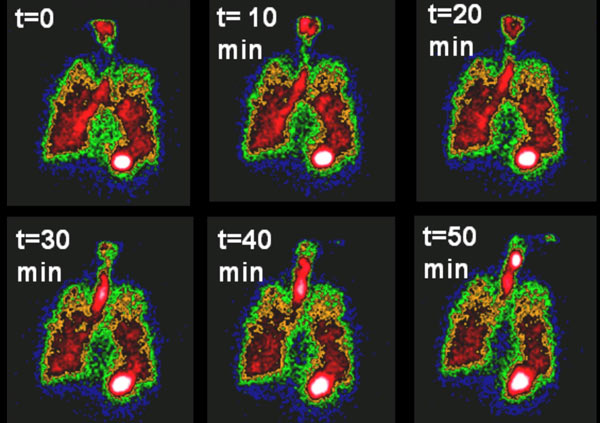

জেব্রাফিশের হার্টের ‘ইসিএম’ (সবুজ)

হার্টের কোথায় কোথায় কার্যকরী হবে জেব্রাফিশের ‘ইসিএম’